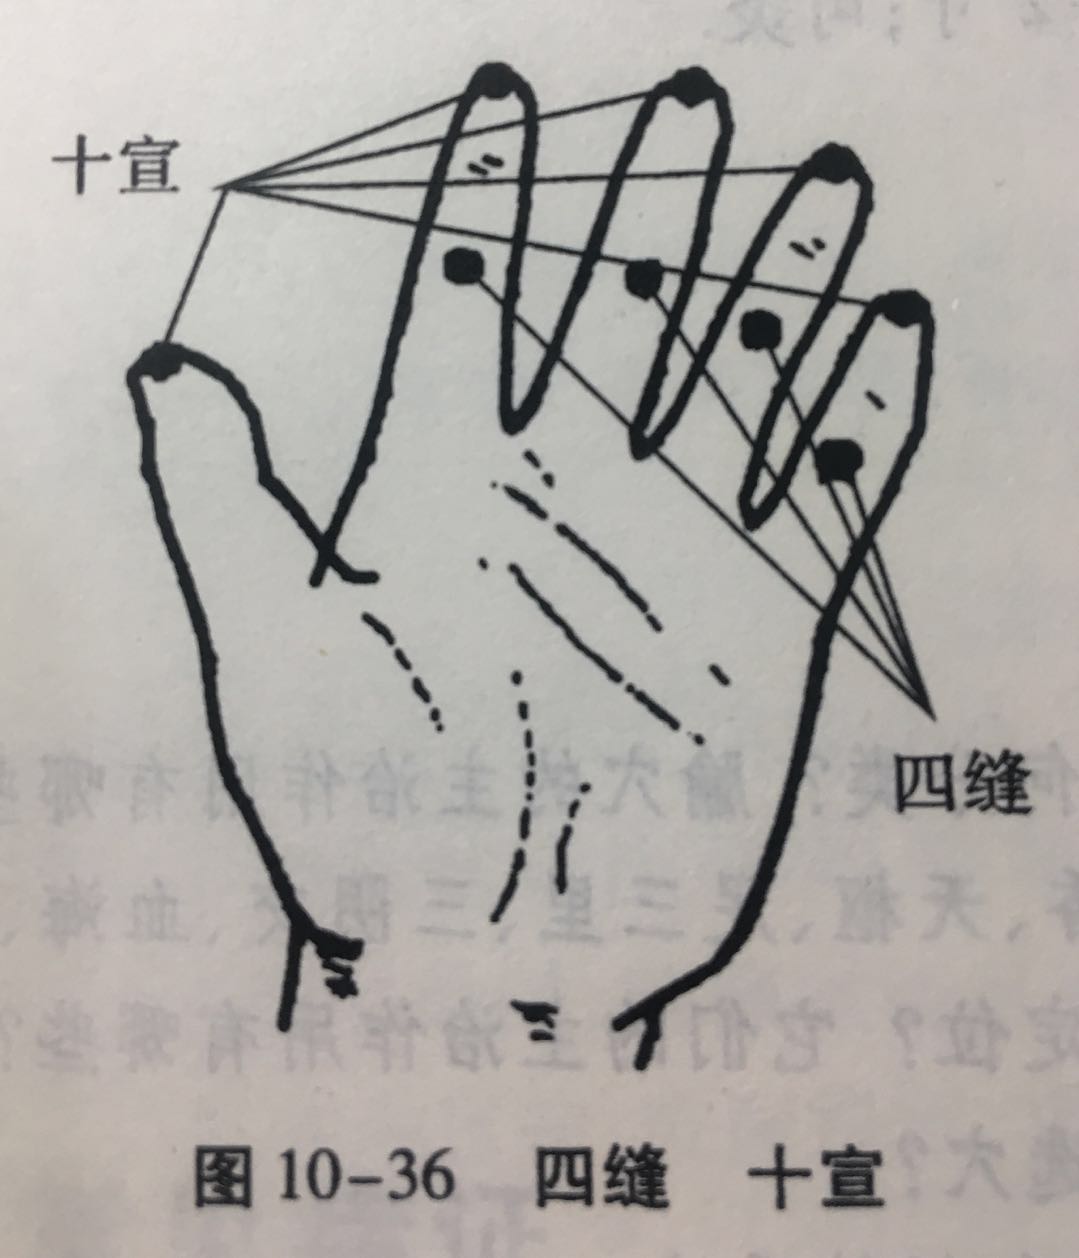

四缝

【定位】 在第 2 至第 5 指掌侧,近端指关节的中央,一手 4 穴,左右共 8 穴(图 10-36)。

【主治】 小儿疳积,百日咳。

【刺灸法】 点刺出血或挤出少许黄色透明黏液。

十宣

【定位】 在手十指尖端,距指甲游离缘 0.1 寸(指寸),左右共 10 穴(图10-36)。

【主治】 昏迷,癫痫,高热、咽喉肿痛。

【刺灸法】 浅刺 0.1 ~ 0.2 寸,或点刺出血。